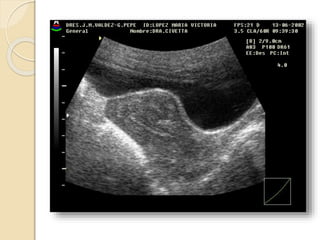

Útero púber: 7cm. 5cm. 4cm

Tamaño: Útero púber:7cm. 5cm. 4cm Dependiendo de la multiparidad la cual aumenta aproximadamente 1 a 2 cm en todas las direcciones